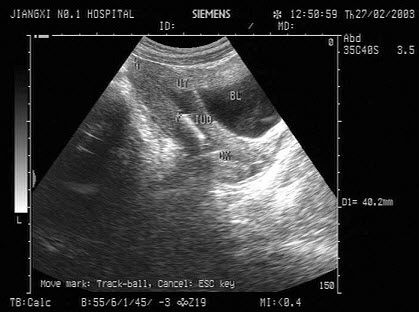

女性,于膀胱输尿管位置见一囊性光团,有规律收缩,增大。如图所示,考虑为()

A.膀胱肿瘤

B.膀胱憩室

C.输尿管结石

D.输尿管囊肿

E.膀胱异物